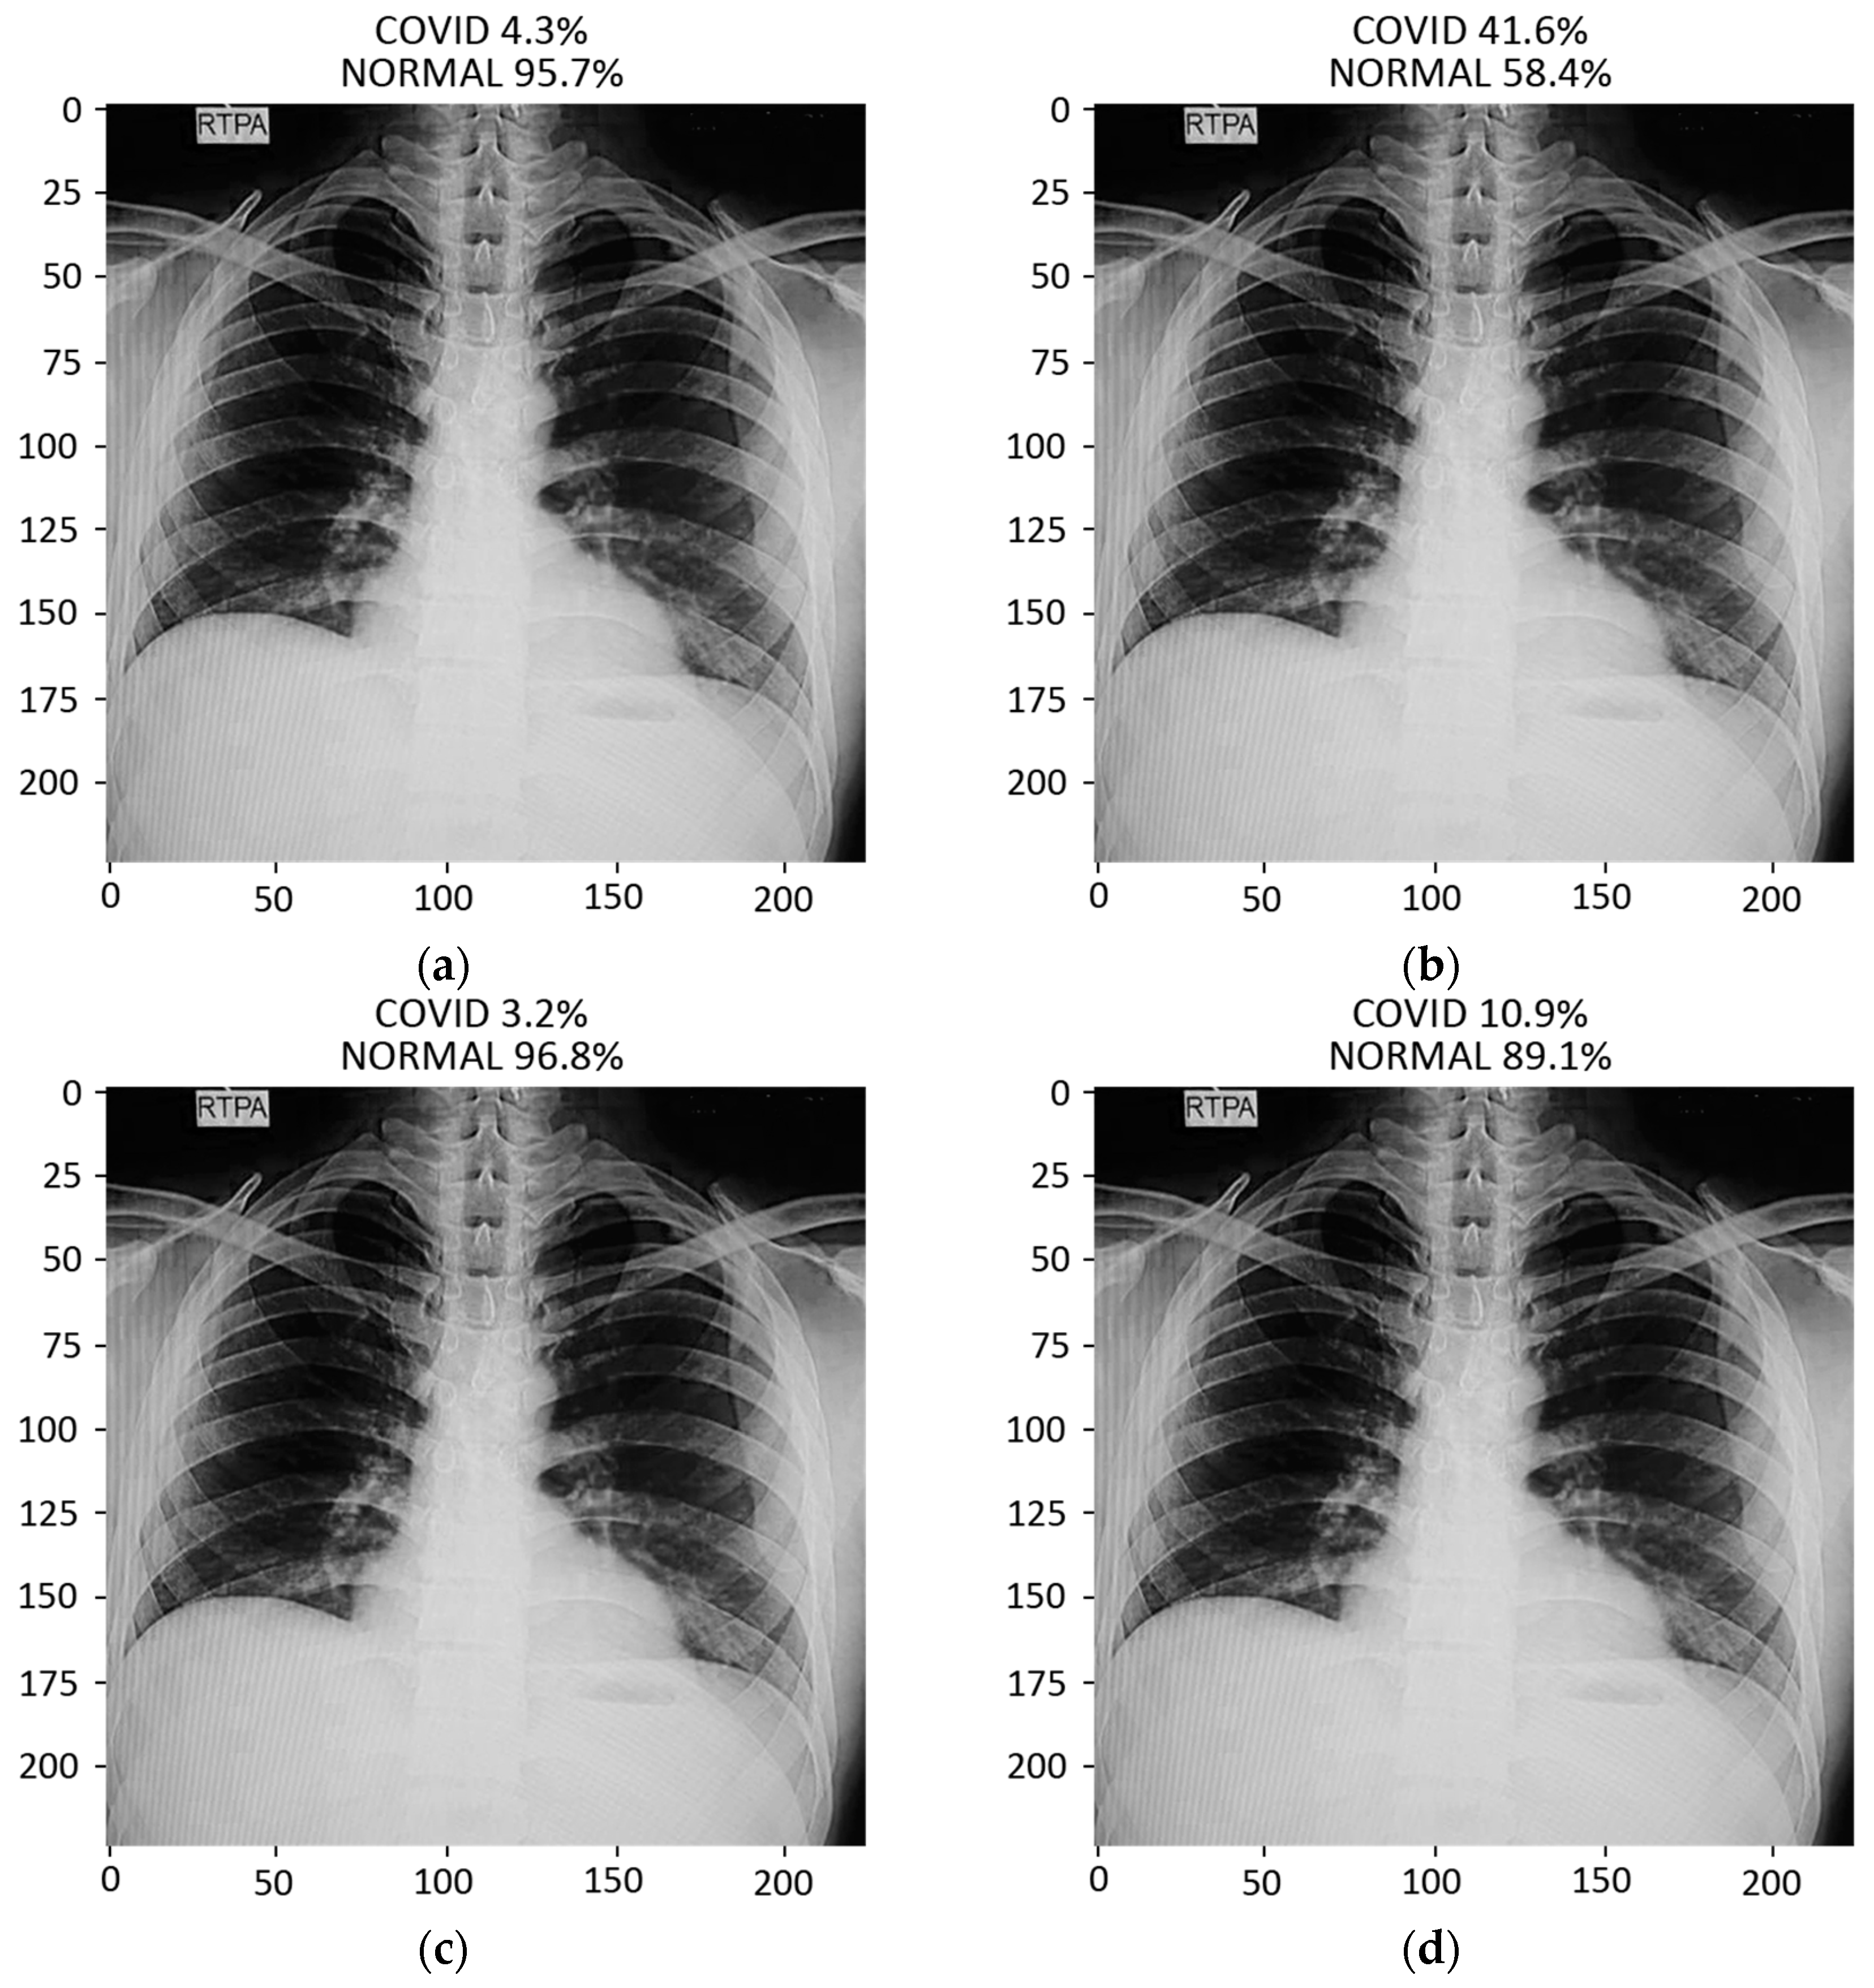

In this study, pulmonary (chest) X-ray images were used for the diagnosis of COVID-19. The dataset was categorized into two main classes, i.e., COVID-19 and normal. A total of 7232 images (3616 COVID-19 + 3616 normal) were accessed from the ‘COVID-19 Radiography Database (available at Kaggle, https://www.kaggle.com/tawsifurrahman/covid19-radiography-database, accessed on 4 May 2021) [30]. From the total images, 70% (5062 images) were used for training + validation, and the remaining 30% (2170 images) were used for testing purposes. The training + validation dataset of 5062 images was further split into a 70:30 ratio, i.e., 3544 (70%) images for training purposes and 1518 (30%) images for validation purposes. The details of the data splitting are given in Table 1. In addition to the dataset accessed via Kaggle, another locally collected dataset of 450 images (COVID-19 + normal) was also used for testing and prediction purposes. This indigenous data of chest X-ray images of Pakistani COVID-19 positive and normal patients have been collected from a local hospital. The samples of normal and COVID-19 X-ray images assessed via the Kaggle database are shown in Figure 1, whereas the samples of the locally collected images are given in Figure 2.

Figure 2.

Samples of local Pakistani verified dataset used for the testing of trained models: (a–c) COVID-19 chest X-rays; (d–f) normal chest X-rays.

The prediction result for a chest X-ray of a local COVID-19-positive patient for each model is given in Figure 13a–d. The DenseNet-121 had the highest probability percentage of COVID-19, i.e., 99.9%. In order to highlight the area where the model is paying the most attention during feature extraction, the Grad-CAM technique was applied. The Grad-CAM results of all four models under study are given in Figure 14. Moreover, the results of the predicted normal patients for each model are shown in Figure 15a–d. Considering these results, the MobileNet has the highest probability of 96.8% for the prediction of a normal chest X-ray.

Figure 15.

Results of prediction on a verified local Pakistani normal chest X-ray: (a) DenseNet-121; (b) VGG16; (c) MobileNet; (d) ResNet-50.